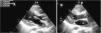

Case reportA 21-year-old man, black, a football player, was admitted via the emergency department with a clinical and laboratory diagnosis suggestive of acute appendicitis. There was no relevant family or personal history. Physical examination showed no abnormalities other than in the abdominal region. He underwent laparoscopic appendectomy under balanced general anesthesia, both of which were uneventful. The patient was extubated at the end of the procedure following reversal of neuromuscular blockade. Immediately after extubation, he developed a setting of respiratory distress, with abundant pink frothy sputum and significant arterial desaturation. Physical examination and chest X-ray revealed the presence of APE (Figure 1). After orotracheal reintubation and connection to a ventilator, the patient was transferred to our unit. Following treatment including high-flow oxygen therapy and administration of intravenous boluses of furosemide and isosorbide dinitrate, he showed rapid improvement and was extubated around four hours later (Figure 2). Other laboratory tests, together with electrocardiographic and echocardiographic assessment (Figures 3 and 4) excluded heart disease. There were no further complications.